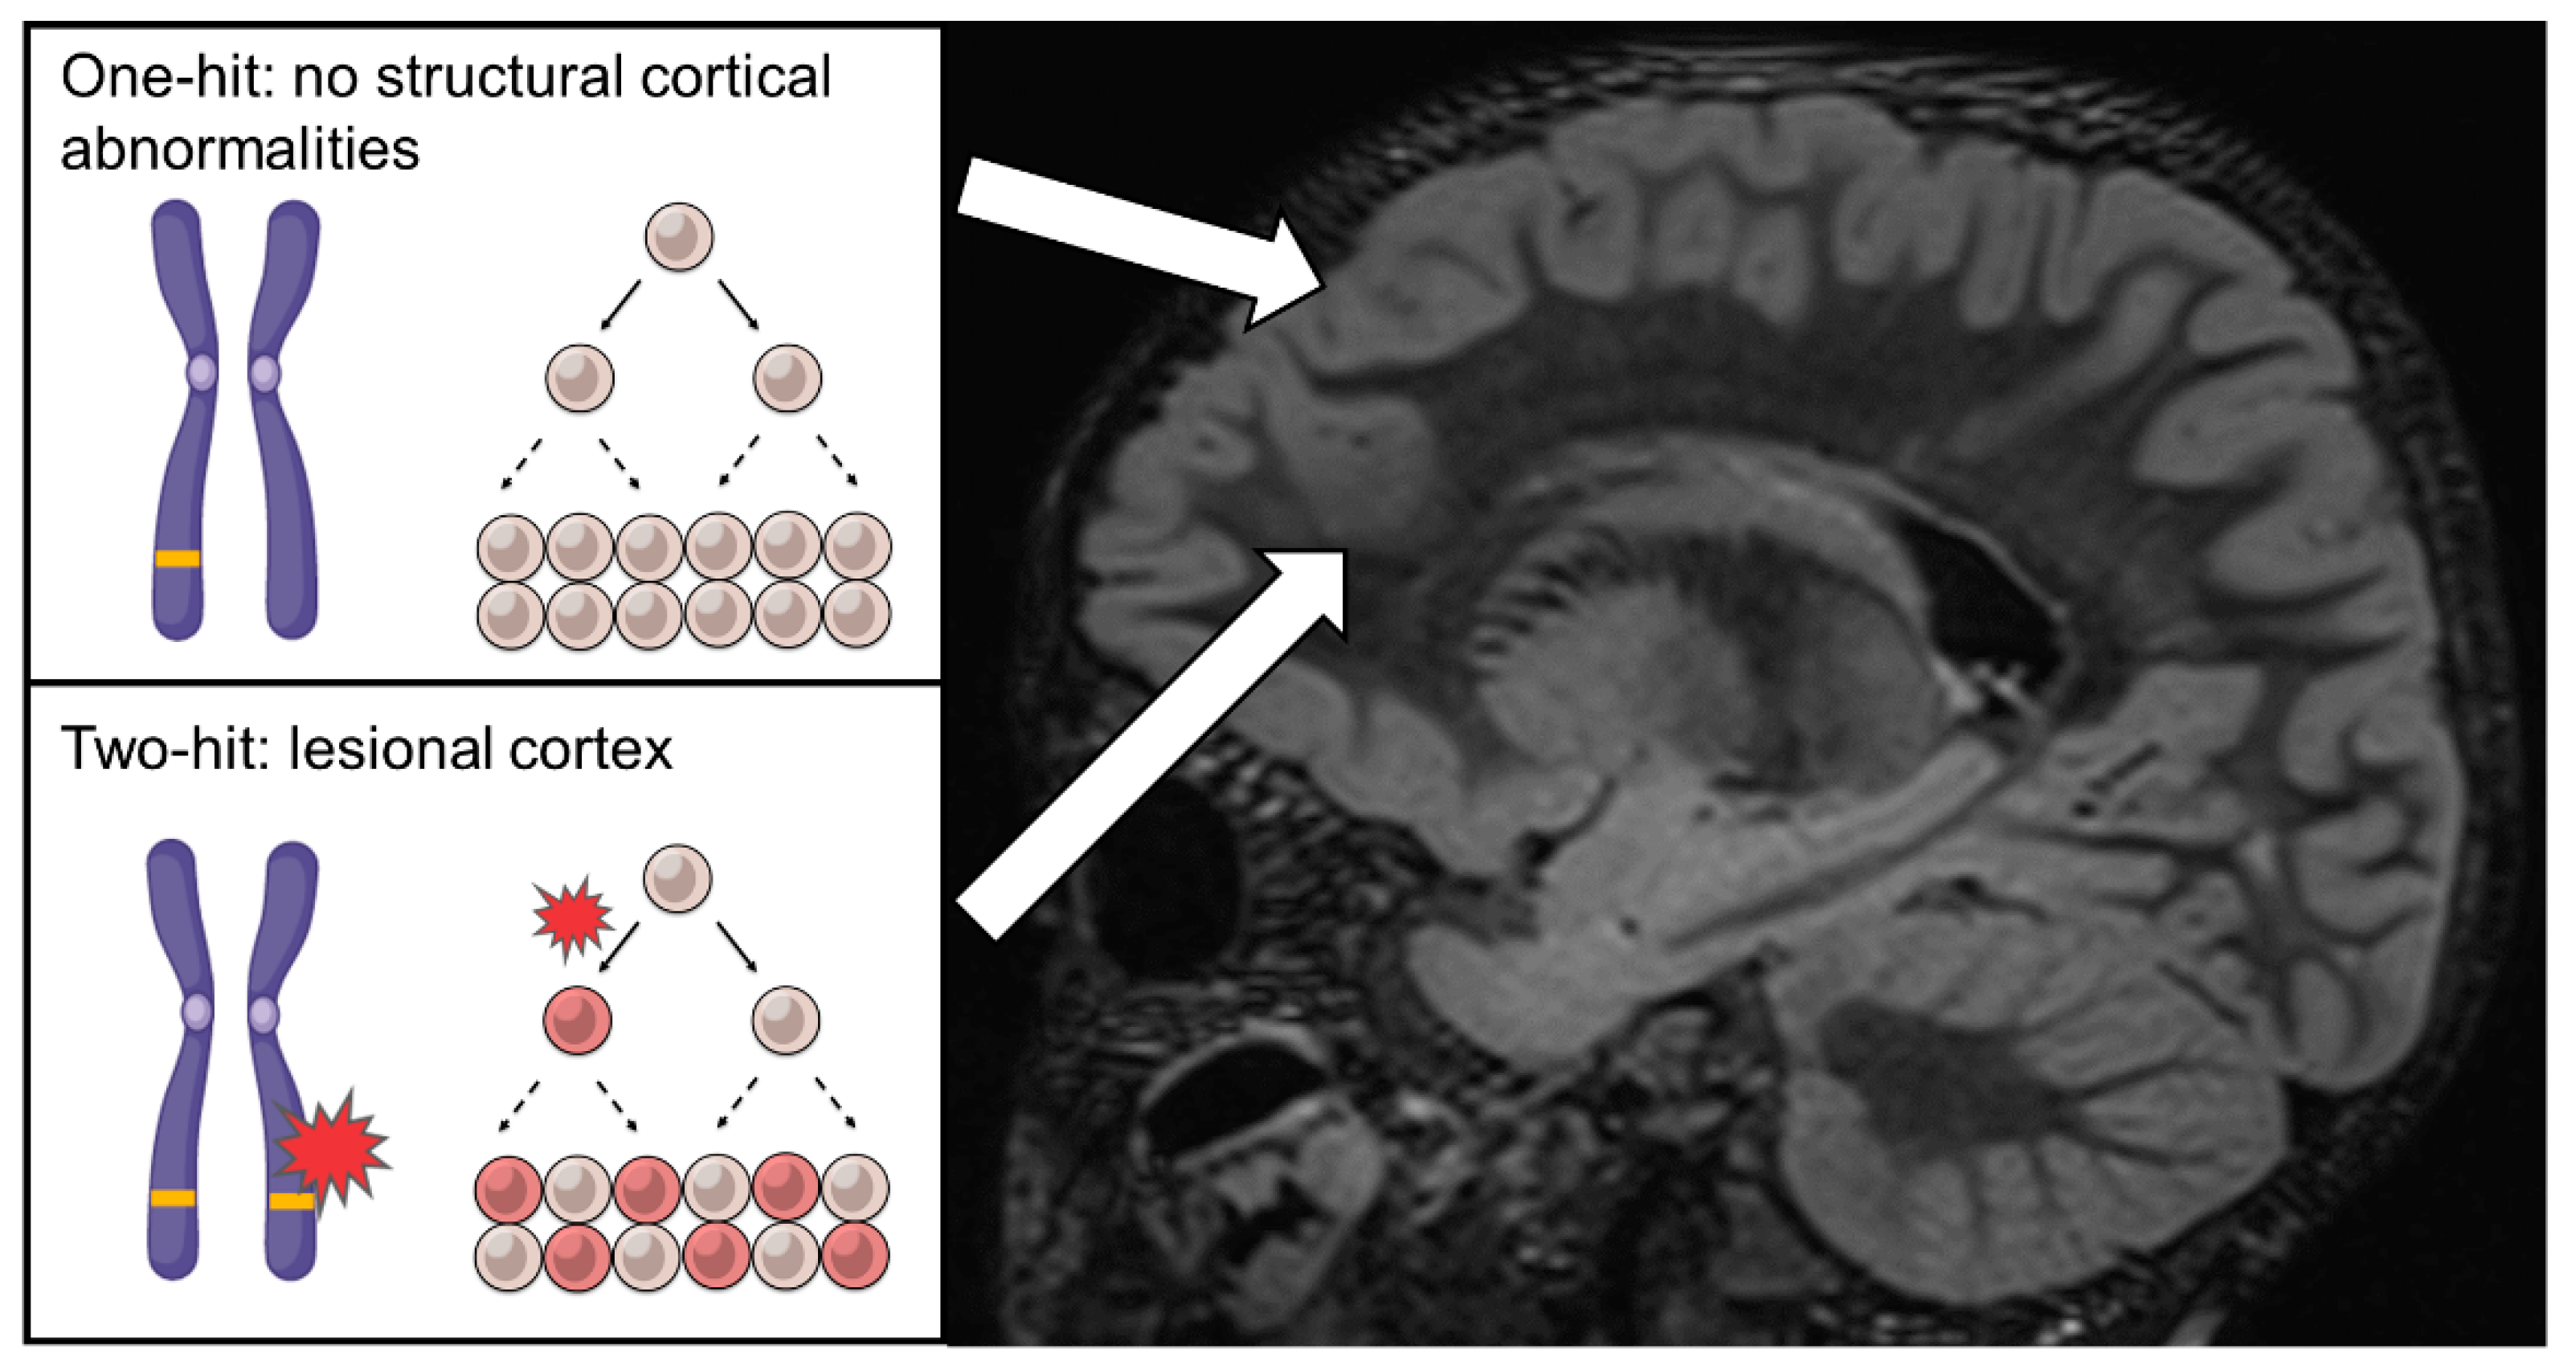

4. The Curious Cases of Familial FCD, Non-Lesional Epilepsy and the Two-Hit Hypothesis—2014

5. First Evidence of Two-Hit Mechanism and Somatic MTOR Variants in FCD—2015~2016

6. Somatic Mosaicism in TSC1/2 and the Continuum of Cortical Dysplasias—2017

7. Confirmation of the Two-Hit Mechanism in FCD and the Identification of Somatic RHEB Variants—2018~2019